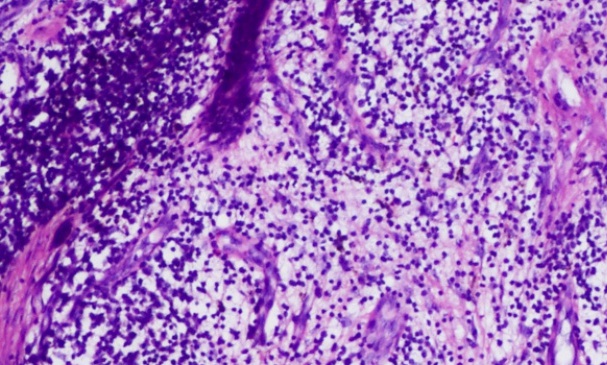

Histopathological examination of sinus tract biopsy showed granulomas in deep dermis, with Langhans giant cells, epitheliod cells and histiocytes, which were suggestive of scrofuloderma, as has been shown in [Table/Fig-4,5].

Chronic inflammatory infiltrate in the Dermis